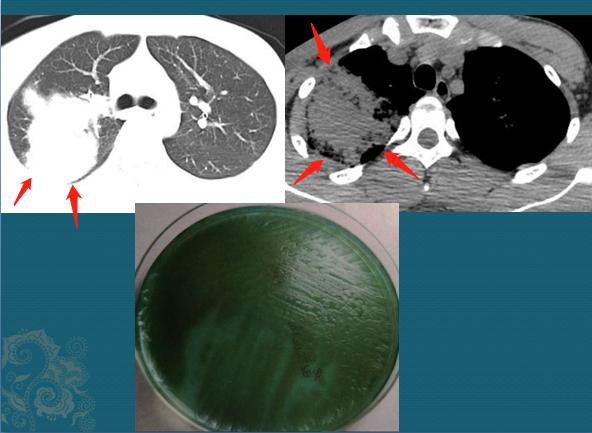

人类的身体是有健康底线的,过度透支会导致早衰,让身体从年轻时就开始走下坡路。最近有一个18岁的网瘾少年,就因为长期熬夜免疫力下降,引发一种严重的细菌感染,肺叶差点被细菌熔化掉:

这个绿色的细菌叫铜绿假单胞菌,它不侵犯健康人,多见于身体虚弱长期住院的病人,比如中性粒细胞缺乏、恶性肿瘤放化疗、长期服用激素、慢阻肺或支气管扩张症的病人,治疗起来很复杂,也很贵!

发生铜绿假单胞菌肺炎后,肺部CT会呈现什么表现?

有些病人病史和症状不典型,而这种感染需要做专业的针对性治疗,否则会有生命危险,所以CT征象很重要!

1.铜绿假单胞菌肺炎早期影像学表现与支气管肺炎相同,为双肺多发的实变影,可以按小叶、亚段或段分布,斑片状或融合灶,其病理特征是血管侵袭和坏死,可见微脓肿、出血和局灶性坏死,所有肺叶均可受累,但其所致社区获得性肺炎以右肺上叶受累为主。

2.某些不常见的影像学表现,可以呈现大叶性实变,多发结节状阴影或网格状表现,需要密切结合病史。

就像这位老爷子,有多年的支气管炎肺气肿,肺部免疫力减退,感染铜绿后发生右上肺为主的病灶,已经融合为大片实变,边缘有模糊的磨玻璃影,内部有坏死和小空洞提示为化脓性炎。后来确诊为铜绿假单胞菌肺炎,因为诊断及时,用药合理,抢救成功了!

这类病人在临床表现常为突然发病,伴有寒战,发热和严重的呼吸困难,咳黄色或黄绿色脓性痰,原有肺部慢性疾病的病人,平时常伴有慢性咳嗽咳痰,当出现黄绿色脓痰,呼吸困难加重及肺功能进行性减退时,应考虑铜绿假单胞菌感染的可能,要及时正确诊治!